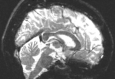

Reversed Gradient Polarity (RGP) methods are commonly used to correct susceptibility artifacts in Echo-Planar Imaging (EPI) [Stehling et al., 1991]. RGP methods acquire a pair of images with opposite phase encoding directions, which leads to a minimal increase in scan time due to the speed of EPI. In a post-processing step, RGP approaches use the fact that the distortion in both images has an equal magnitude but acts in opposite directions to estimate the field map (see Figure 1) [Chang and Fitzpatrick, 1992, Bowtell et al., 1994]. The field map is then used to estimate a distortion-free image.

Refer to captionRefer to captioninput images+v𝑣+vv𝑣-vRefer to captionoptimizeRefer to captionfield map b𝑏bRefer to captionapply modelRefer to captioncorrected image \mathcal{I}

Figure 1: The Reverse Gradient Polarity correction paradigm. Two images are acquired with opposite phase encoding directions, +v𝑣+v and v𝑣-v. These two images are used to estimate the field map b𝑏b, and the distortion correction model [Chang and Fitzpatrick, 1992] is applied to obtain a corrected image \mathcal{I}.